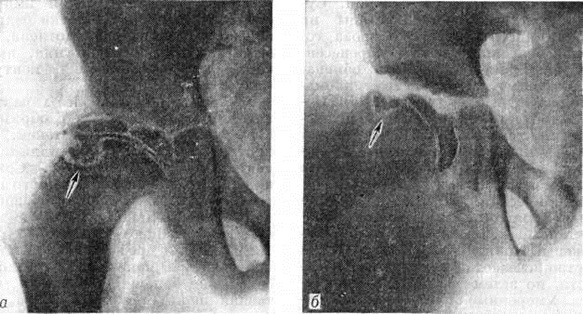

Третья стадия, наиболее характерная для Пертеса болезнь,— стадия с образованием секвестроподобных теней. Некротические массы расщепляются и постепенно рассасываются. Сохранившиеся островки гомогенного некроза, окружённые вновь образованной соединительной тканью и хрящом, напоминают секвестры (рисунок 2, а). Если ребёнок продолжает пользоваться конечностью, головка бедра ещё больше уплощается, суставная щель становится шире, чем во второй стадии. Щель эпифизарного хряща расширяется, приобретает извилистые рыхлые контуры. Шейка утолщается и укорачивается в результате нарушения процессов энхондрального роста. В тяжёлых случаях в субхондральных её отделах выявляются очаги разрежения. Соответственно деформации головки бедра изменяется и форма вертлужной впадины, её крыши. Проксимальный конец бедра может быть смещён в положение небольшого подвывиха кнаружи и кверху.

Четвертая стадия — стадия восстановления структуры (рисунок 2, б). Секвестроподобные тени не определяются, но структура головки долгое время остаётся неравномерной, постепенно приобретая нормальный губчатый рисунок. Деформация головки сохраняется на всю жизнь. Чётких рентгенологических границ между описанными четырьмя стадиями не существует.

Рис. 2.

Прямые рентгенограммы правого тазобедренного сустава ребёнка 12 лет с болезнью Пертеса в процессе лечения: а — эпифиз головки бедренной кости фрагментирован, уплощён, стрелкой указан новый участок некроза в шейке бедра ниже ростковой зоны (третья стадия заболевания); б — целость эпифиза восстановилась, но он остаётся уплощённым, смещённым книзу; в укороченной и утолщённой шейке бедра некроз (указан стрелкой) сохранился (четвертая стадия заболевания).